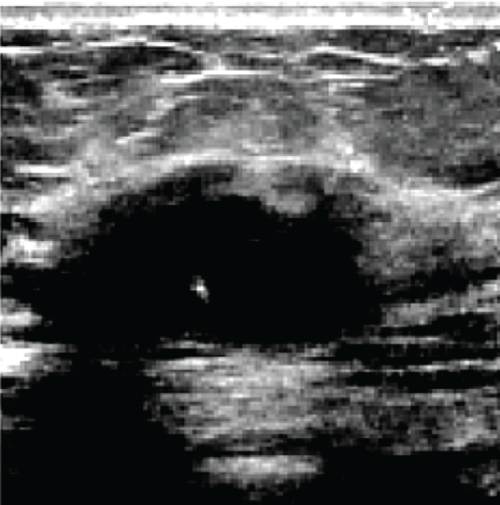

In the sequence of processing ultrasound images, Fig. 20 shows the original input image acquired from an ultrasound scan from the dataset provided in [41]. This image is subsequently resized for standardization, as illustrated in Fig. 21, to maintain consistency throughout all following processing processes. Next, Fig. 22 shows the filtered version of the picture, which has been filtered bilaterally to minimize noise while keeping critical edge details required for accurate anatomical structure detection. Fig. 23 shows further picture enhancement using the Non-Local Means (NLMS) filter, a method chosen precisely for its ability to preserve detailed details while increasing contrast. Finally, Fig. 24 shows the contour of the tumor, which clearly defines the afflicted area and serves as an input for feature extraction and subsequent classification stages.

Figure 20: Original image (Ultrasound Scan)